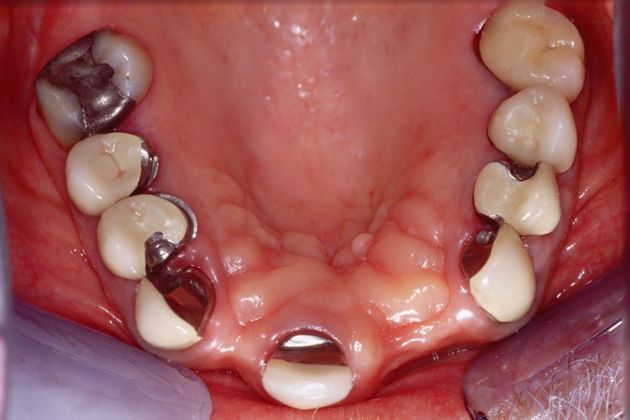

Procedures; Bite correction, gum recontouring, implants, whitening and crowns.

This healthcare professional had been wearing a removable appliance for years. He had a deep overbite and the anchor teeth for his appliance were breaking down. His main concern was to restore the functionality of his teeth with a fixed, long term solution.